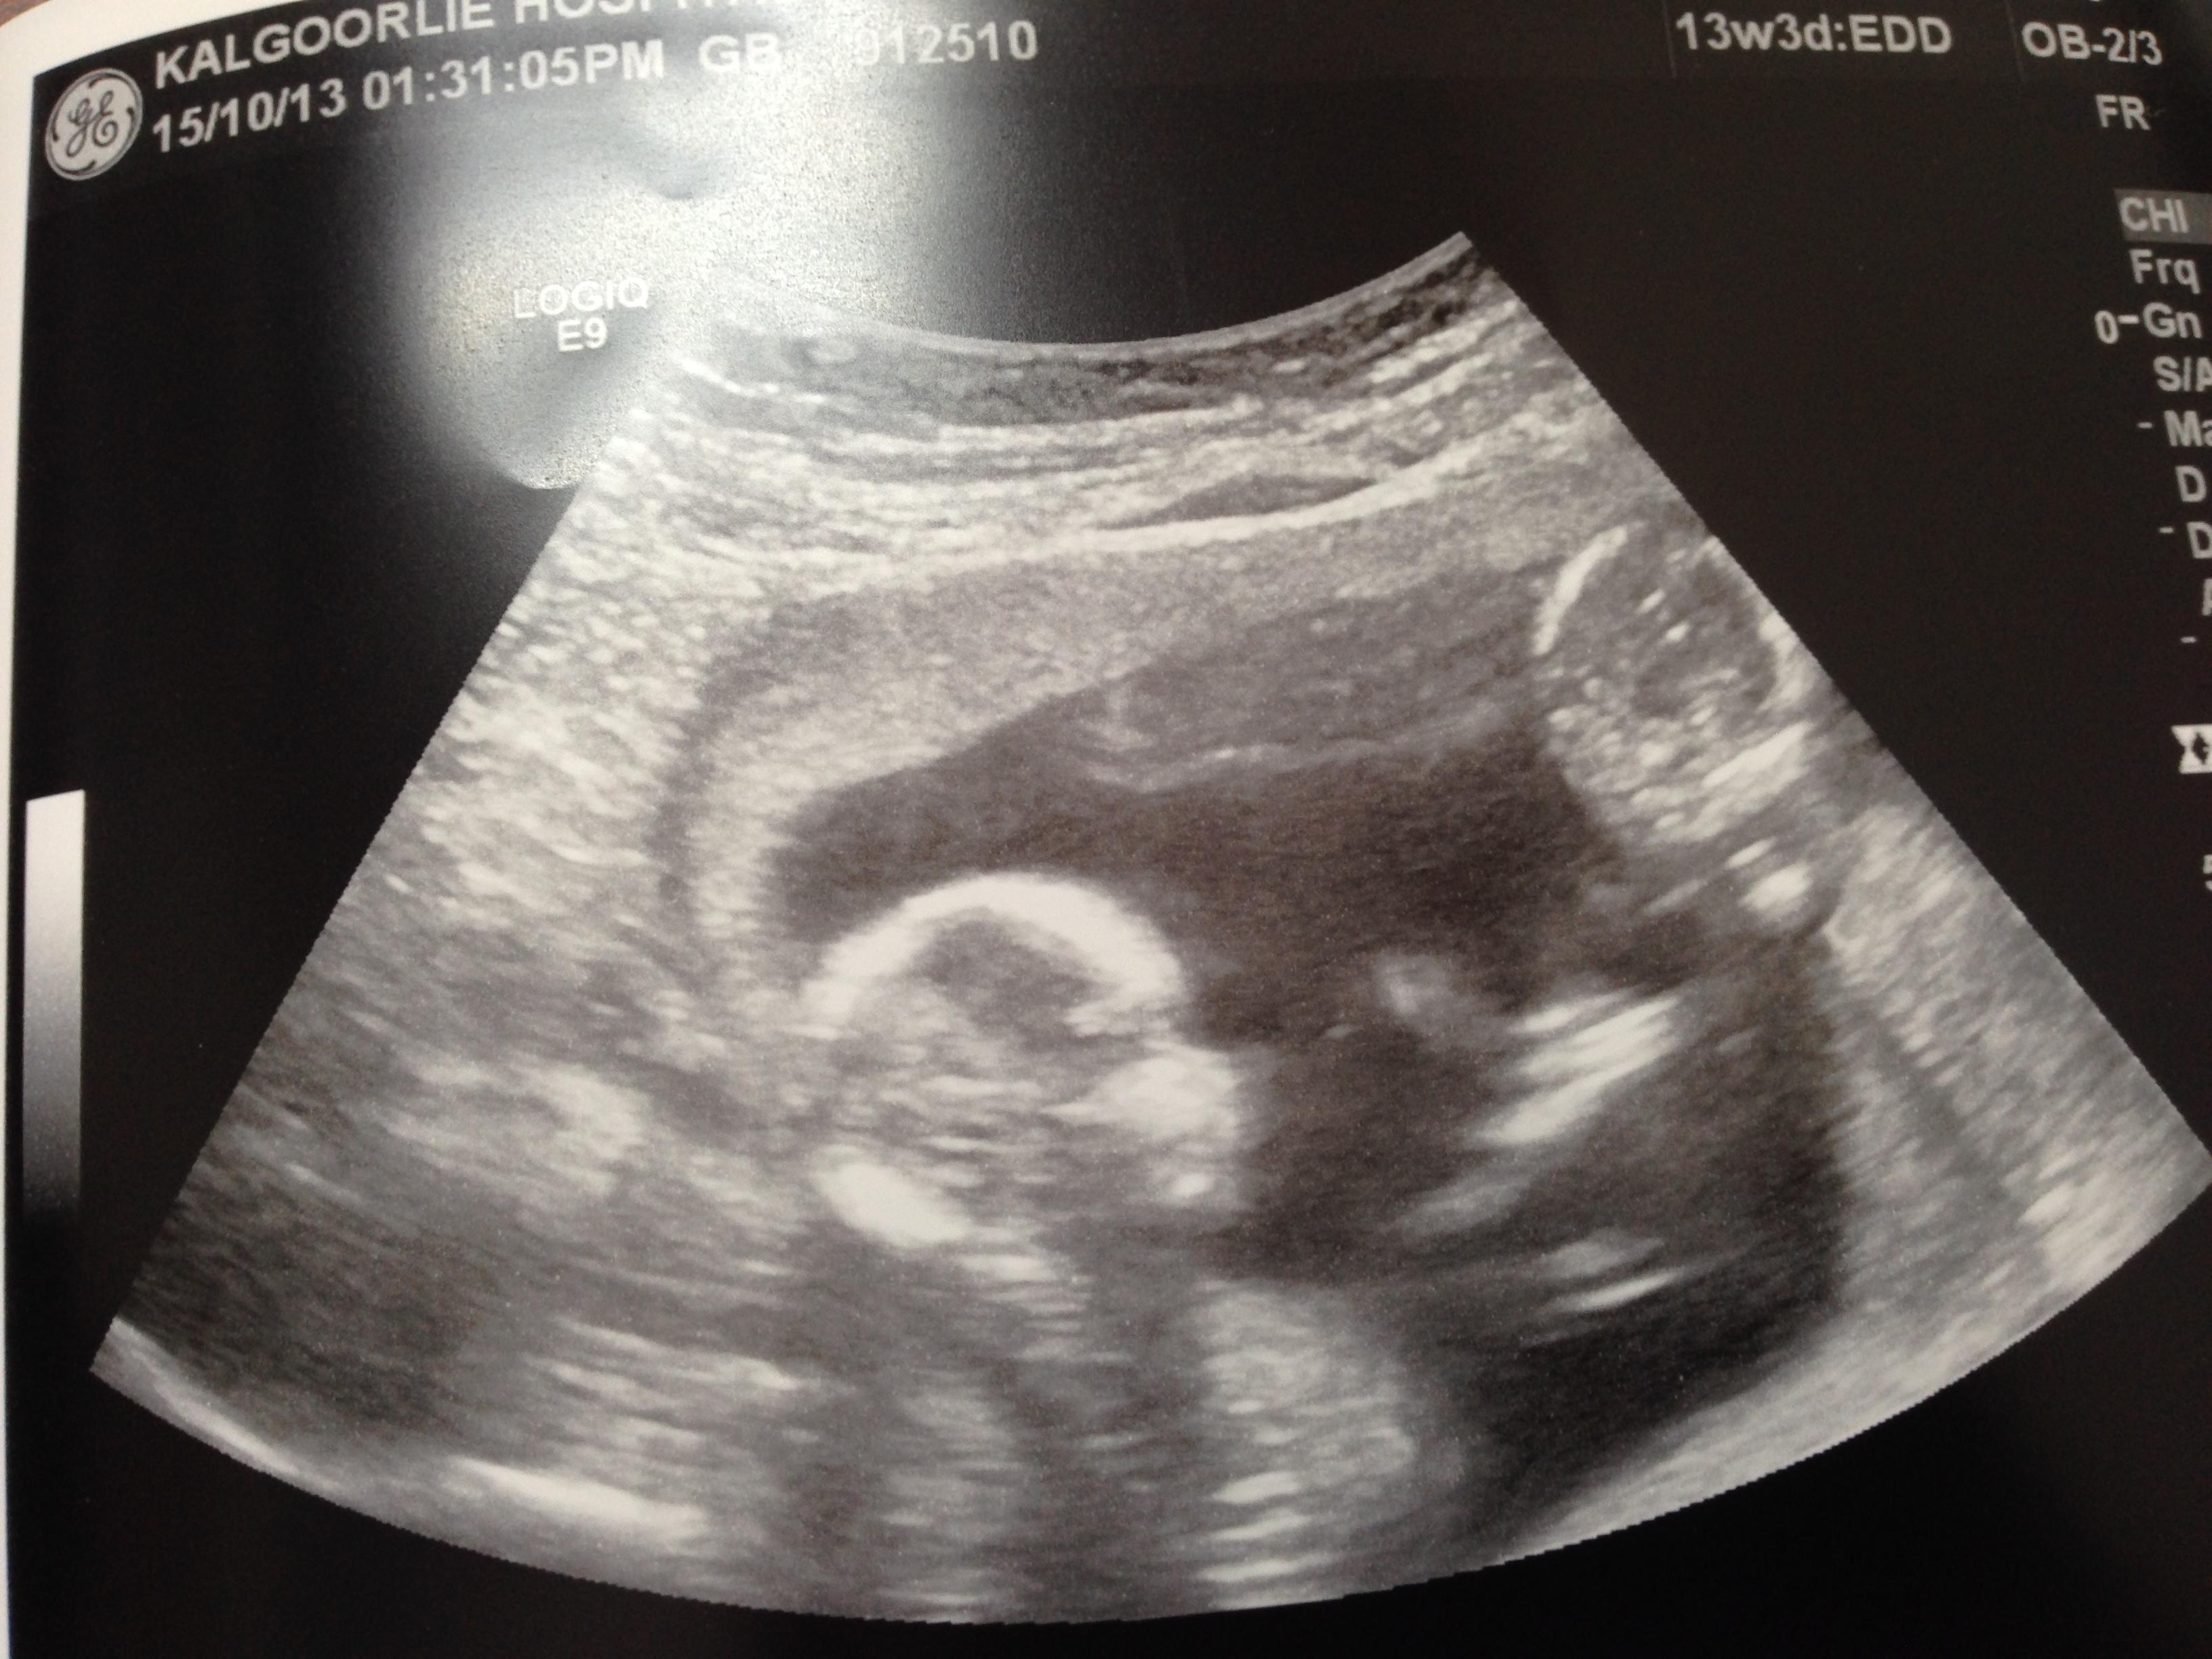

So a couple of weeks ago, no one in Kalgoorlie could find this membrane between the two babies and from that we were told that there is a 5% chance of us having the babies in Kalg as the possibility of them being born to full term (36 -38 week) was not even in the picture, this put us on to the ‘High Risk Pregnancy’ range which to date we still are. We would have probably be put on bed rest at 30 weeks in hospital in Perth, until they are born at either 32 weeks or when ever a complication would of came up. They also would have injected me with something to help develop their lungs to increase their risk of surviving. But after seeing Dr McCullam, he referred me to a senior sonographer that comes from King Edward to Kalg once a month, to see if she could find the membrane. Alas after an hour and a half and two different types of scans, we found one and it was wrapped up against Twin 2 head. She could also tell that we were going to be in for a bumpy ride as from scan, there was not enough fluid around the Twin 2 and a heap of fluid around Twin 1. She also couldn’t find Twin 2’s bladder as it peed just as she was taking the measurements (she called it a little so and so for that – they were cheeky monkeys the whole time) So without the fluid and seeing the bladder she has told us that the babies have developed a complication called Twin to Twin Transfusion Syndrome or TTTS. So she rung her bosses at King Edward and got us an appointment that next week for a scan and a possibility of laser surgery the day after. We were off to Perth!

So what is TTTS – it is a very complex problem that affects around 15% of mono type of twin pregnancies. It can appear at any time throughout and ours is a bit different as it has occurred so early in the pregnancy (around 13 weeks) where it is usually picked up around 16-26 weeks. It means that we have a donor twin (Twin 2) and a recipient twin (Twin 1), where Twin 2 is pumping the blood for itself but for also the other, and while doing that it is using all that energy in that process instead of looking after itself and using that energy to grow itself. It is also trying to create fluid to be around it but due to the lack of growing, it’s bladder is too small to allow it to create the fluid that is needed. Without this blood supply and fluid around the twin 2, it is at a very high risk of dying due to lack of blood or may be born and have a blood transfusion due to being anemia (lack of blood).

So when we got to Perth (after a slight delay – due to the doctor we were meant to see was hit by a car the day before, so they had to rearrange us to the Friday, which meant we didn’t know if the laser surgery could be done or not the next day) We saw the Doctor and also Prof Jan Dickenson (who didn’t talk to us) and they done a scan. Doctor was a nice guy and asked us what we knew so far. So apart from what we have been told, it was that we may have TTTS and we were there at King Edward to get a confirmation on this. After a long time looking at the twins, (Doctor was funny as it was like he was playing a video game and turning his head to see around corners and zooming in, he was getting closer to the screen.) we have found that Twin 1 is around 138grams and Twin 2 is around 113 grams. Now this may not seem a lot to us in the outside world but that difference in weight to the docs – it is a big deal. They also spent a little bit of time talking to themselves and what we presume was checking out the blood flow. They didn’t talk much about that bit to us so we are not too sure what the norm is or anything. After they had their little chat we were then told what we didn’t really want to hear. That the TTTS was at Stage 3, this is more than we thought.

Stage 1: no/little fluid around one Twin (Twin1 had over 10cm of fluid [the norm is under 8cm] Twin2 has only 1cm and that was near his belly/or head).

Twin 1